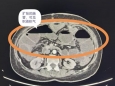

五院主诊 | 内镜外科组:因为肠梗阻,她近一个月没有正常吃饭了

“医生,我什么时候能吃点东西?”“哪怕喝一口鸡汤也好……”50岁的谢女士,已经近一个月没能正常吃饭了。一年前,她查出子宫恶性肿瘤,做了手术和放化疗,后来又因为输尿管堵塞放了输尿管支架。半个多月前,她因肠梗阻在外院做了结肠造口手术,没想到梗阻再次出现,于是转到了成都市第五人民医院普通外科。在医院保守治疗一周后,谢女士肠梗阻的情况还是...